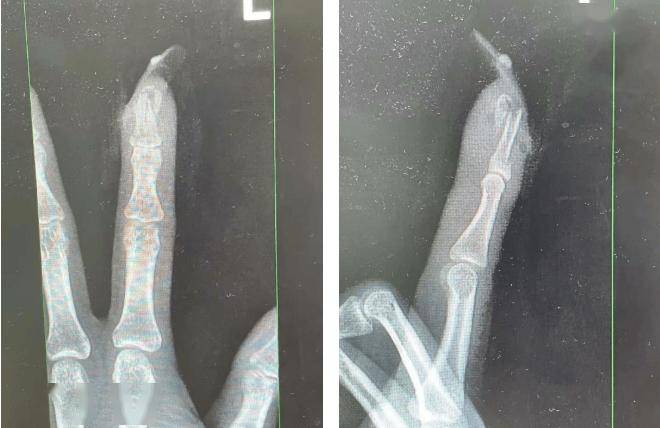

但在这光鲜亮丽的背后,却隐藏着一系列健康隐患。之前就有人因此进了医院……某女士带着新骑电动车时意外摔了一跤......

美甲时的打磨、去死皮很容易造成皮肤微小破损。如果美甲工具消毒不彻底,病毒就可能“趁虚而入”,会增加美甲爱好者患上绿甲(铜绿假单胞菌感染)、甲沟炎以及甲真菌病的风险。

特别是锉刀打磨等操作会使指甲变薄,处于屏障功能受损状态,给予病菌更多的入侵机会。